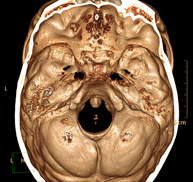

- Neurorradiología

- TC Cráneo

Prueba radiológica que consiste en obtener imágenes del cráneo de alta definición anatómica (tronco cerebral, cerebelo, cerebro, calota craneal, etc.), mediante el empleo de un equipo de TC (Tomografía Computarizada).Indicaciones: traumatismos, cefalea, trastornos de la memoria, pérdida de fuerza súbita en una extremidad o mitad del cuerpo.